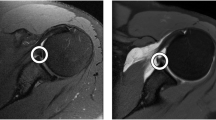

The mean and standard deviation RMSE between the aligned cropped HR-MRI masks and the manually segmented CT masks was 1.34 mm ± 0.26 mm. Figure 5 depicts the 3D model from a HR-MRI mask, the CT mask and the color-coded absolute error surface distance map on the CT mask between the HR-MRI and CT masks of a patient with an RMSE of 1.54 mm.

3D models from a patient with RMSE of 1.54. (a) 3D model of the HR-MRI-mask, (b) 3D model from CT, (c) color-coded map of absolute error surface distance between HR-MRI and CT 3D-models (blue = 0 mm, to yellow ≥ 5 mm).

The RMSE of the test-patients’ 3D high resolution models of the scapula (N = 10) compared to CT was 1.34 mm ± 0.26 mm. Figure 4 shows a typical distance map of an example patient with average RMSE. Visually, large surface differences between the HR-MRI models to the CT models were located in the periphery and mainly at the medial parts of the scapula. In regions where the morphology measurements are performed, such as the glenoid and the acromion, these errors were significantly lower. This might be due to the fact, that these regions are visualized in the MRI along all orientations whereas the structures in the periphery are often outside the FOV of one or multiple planes.